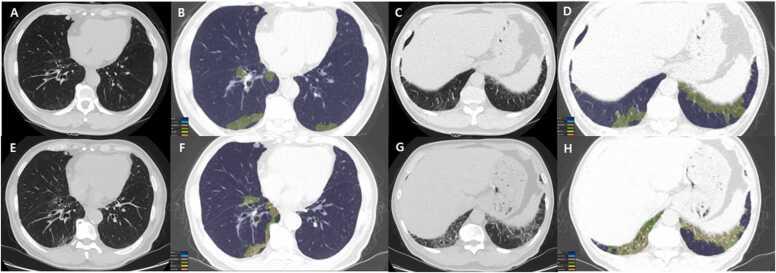

Connective tissue diseases (CTDs) demonstrating features of interstitial lung disease (ILD) include systemic lupus erythematosus (SLE), rheumatoid arthritis (RA), systemic sclerosis (SSc), dermatomyositis (DM) and polymyositis (PM), ankylosing spondylitis (AS), Sjogren syndrome (SS), and mixed connective tissue disease (MCTD). On histopathology of lung biopsy in CTD-related ILDs (CTD-ILDs), multi-compartment involvement is an important clue, and when present, should bring CTD to the top of the list of etiologic differential diagnoses. Diverse histologic patterns including nonspecific interstitial pneumonia (NSIP), usual interstitial pneumonia (UIP), organizing pneumonia, apical fibrosis, diffuse alveolar damage, and lymphoid interstitial pneumonia can be seen on histology in patients with CTD-ILDs. Although proportions of ILDs vary, the NSIP pattern accounts for a large proportion, especially in SSc, DM and/or PM and MCTD, followed by the UIP pattern. In RA patients, interstitial lung abnormality (ILA) is reported to occur in approximately 20-60% of individuals of which 35-45% will have progression of the CT abnormality. Subpleural distribution and greater baseline ILA involvement are risk factors associated with disease progression. Asymptomatic CTD-ILDs or ILA patients with normal lung function and without evidence of disease progression can be followed without treatment. Immunosuppressive or antifibrotic agents for symptomatic and/or fibrosing CTD-ILDs can be used in patients who require treatment.

表现为间质性肺疾病(ILD)特征的结缔组织病(CTD)包括系统性红斑狼疮(SLE)、类风湿关节炎(RA)、系统性硬化症(SSc)、皮肌炎(DM)和多发性肌炎(PM)、强直性脊柱炎(AS)、干燥综合征(SS)以及混合性结缔组织病(MCTD)。在CTD相关ILD(CTD-ILD)的肺活检组织病理学检查中,多部位受累是一个重要线索,若出现这种情况,应将CTD列为病因鉴别诊断的首要考虑。CTD-ILD患者的组织学检查可见多种组织学模式,包括非特异性间质性肺炎(NSIP)、寻常型间质性肺炎(UIP)、机化性肺炎、肺尖纤维化、弥漫性肺泡损伤和淋巴细胞间质性肺炎。尽管ILD的比例各不相同,但NSIP模式占很大比例,尤其是在SSc、DM和/或PM以及MCTD中,其次是UIP模式。据报道,RA患者中约20%-60%会出现间质性肺异常(ILA),其中35%-45%的患者CT异常会进展。胸膜下分布以及基线时ILA受累程度较高是与疾病进展相关的危险因素。无症状的CTD-ILD或ILA且肺功能正常且无疾病进展证据的患者可以不进行治疗而进行随访。有症状的和/或纤维化的CTD-ILD患者若需要治疗,可使用免疫抑制剂或抗纤维化药物。